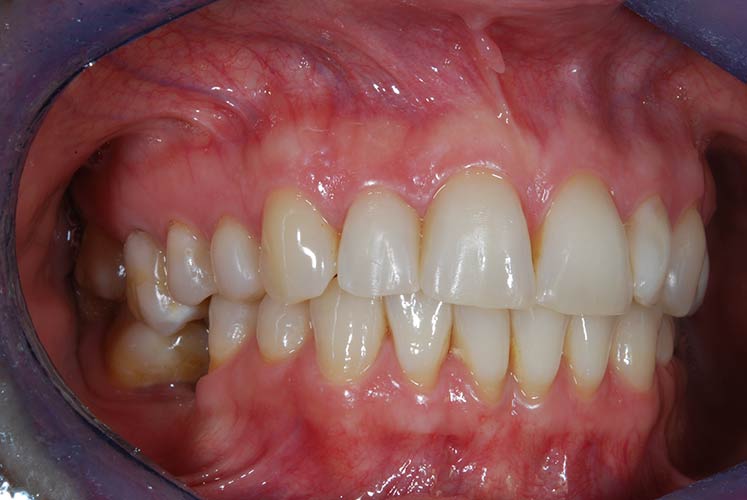

Con protesi fissa superiore e protesi fissa inferiore

I denti irrecuperabili dell'arcata superiore ed inferiore del paziente di anni 65 sono stati sostituiti da 10 impianti, cioè protesi radicolari endo-ossee che sostengono le protesi fisse superiore ed inferiore.